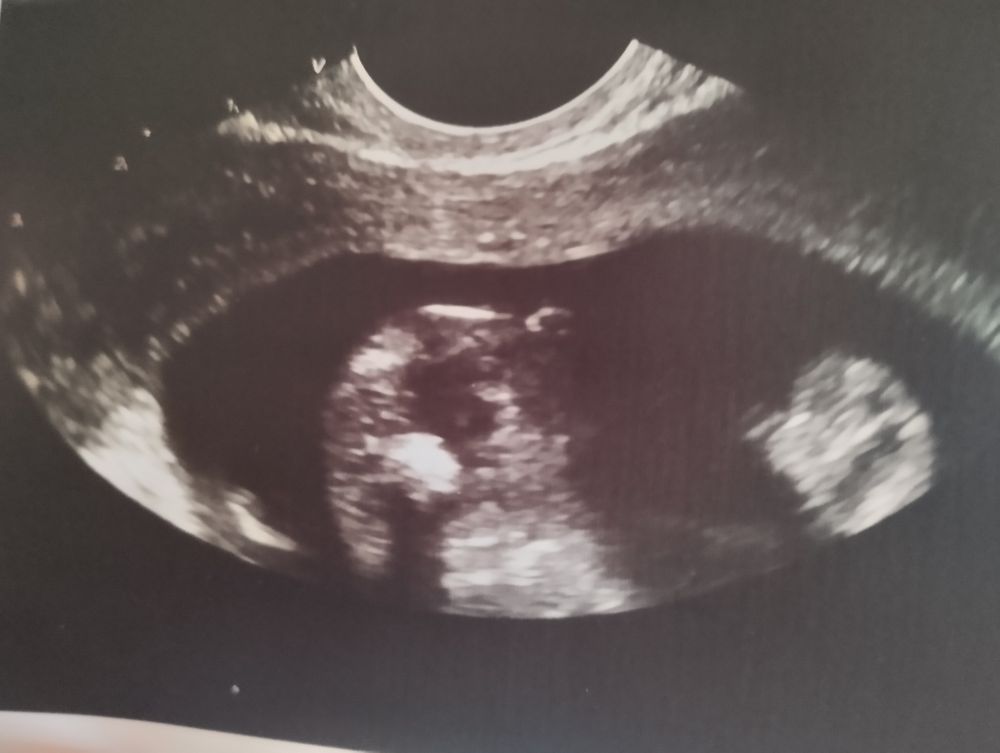

Кристина, вот я о том же, что прошлые две беременности, там прям отчетливо было видно писюны, их не спутать было, а в этот раз, вообще на это не похоже. Вот прикрепила с прошлой беременности,ну тут явно было не спутать Изображение

Юлия Сочинская, вот тут и слепой увидит 😂

Ирина Мороз, она только предположение сказала, что похоже на девочку, потому что не видит машонку и писюн. Вот как мальчики выглядят, я уже видела в предыдущих беременностях, а тут вообще ничего не понятно, хоть она мне и объясняла🙈 хотелось бы конечно верить, что девочка, после двух парней то, но есть сомнения😁